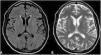

The initial immunosuppression regimens were IV methylprednisone taper starting at a dose of 500mg IV on post-operative day (POD0), tacrolimus induction on POD0, and mycophenolate mofetil on POD 0. Tacrolimus dosing was titrated to target a trough level between 5 and 10μg/L. On POD2, he was noted to be mildly confused. This became more pronounced on POD3 when he was not oriented to self, time or place. He was unable to remember his own name, recognize his wife, recall his home address, or identify where he was. Other than memory loss, the patient had an inappropriate affect and general indifference to his condition. The neurology service was consulted to investigate the acute-onset confusion and amnesia. His cranial nerve, cerebellar, motor and sensory exams were grossly normal. Serum sodium was normal between 135 and 145mmol/L in the post-op period. Septic work up was negative for any infectious etiologies. An initial CT of the head on POD3 was negative for intracranial abnormalities. Based on the clinical presentation and the unremarkable CT scan, a diagnosis of post-operative delirium was made. A follow-up MRI of the head on POD4, however, showed patchy high signal within the central pons on T2 FLAIR and B1000 images with two tiny associated microhaemorrhages, highly suspicious for central pontine myelinolysis. There was also possible mild high T2 FLAIR signal within the caudate and lentiform nuclei which could be related to extra pontine myelinolysis (Figs. 1 and 2). By this time, however, the patient had recovered fully i.e. cognitively normal and fully ambulatory. Post-op delirium was the most likely diagnosis. The patient was discharged home shortly thereafter. In the following months up to now, he continues to function well.

Axial (A) T2 FLAIR and (B) T2 weighted images demonstrate abnormal high signal in the central pons with sparing of the periphery. (C) Axial B1000 diffusion weighted images demonstrate correlating mildly increased signal without evidence of restricted diffusion on the ADC map (not shown) consistent with T2 shine through.